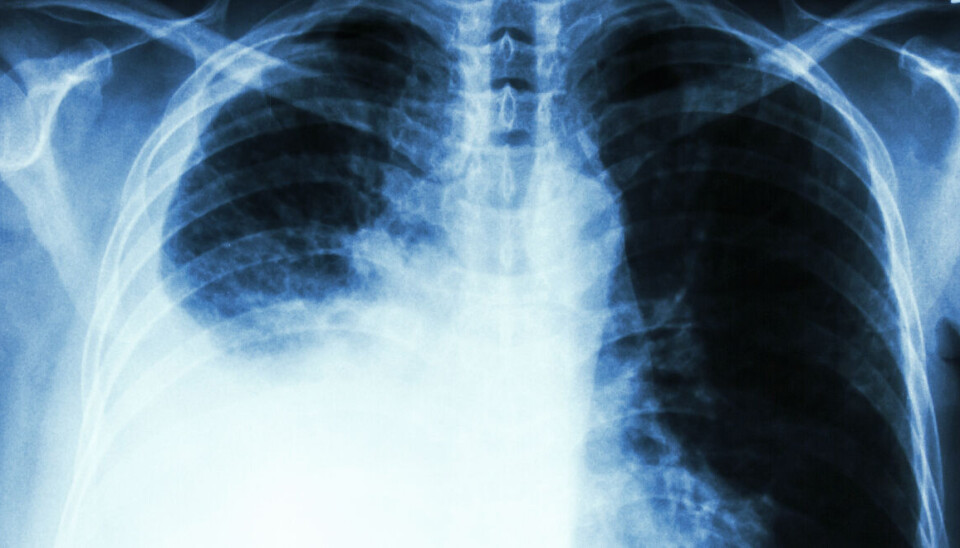

Hvor mange må dø før lungekreftscreening innføres?

Lungekreft står forover fem prosent av alle dødsfall i Norge. Tidlig oppdagelse øker muligheten for overlevelse.

I 2023 ble det registrert 3 319 nye tilfeller av lungekreft, og totalt 2 141 døde av sykdommen. Det utgjør over fem prosent av alle dødsfall i landet. Lungekreft oppdages dessverre ofte for sent. Kun 30 prosent overlever fem år etter diagnosen. Dersom kreften oppdages tidlig, øker denne overlevelsen til 68 prosent. Derfor ser vi svært positive resultater i andre land som har nasjonale screeningprogram for lungekreft.